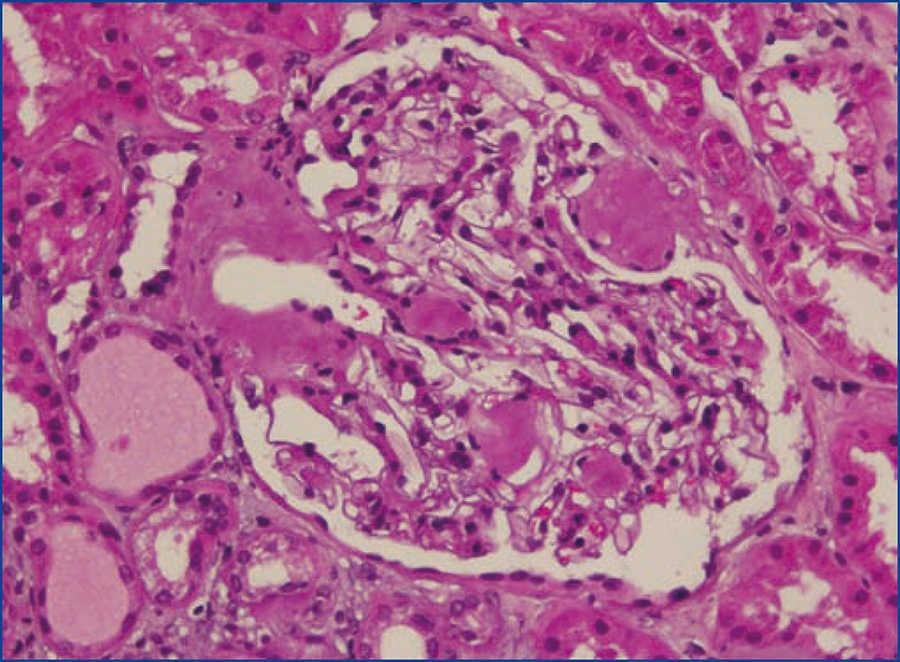

Se decide realizar una biopsia renal, que muestra 26 glomérulos, de los cuales 17 están esclerosados. En algunos de los glomérulos no esclerosados se observan muy focales depósitos nodulares de material hialino eosinófilo, acelular y débilmente ácido peryodico (PAS+) más frecuente en el polo vascular (figura 1), material que se observa también y en mayor cantidad en intersticio y en pared de arterias y arteriolas (figura 2). Este material se tiñe con la técnica de rojo congo (figura 3 y figura 4), tinción que desaparece tras el tratamiento con permanganato, y muestra birrefringencia verde manzana con luz polarizada. Con técnicas de inmunohistoquímica, el material acelular muestra tinción con amiloide A (figura 5). Se observa además una fibrosis intersticial y atrofia tubular moderadas (20 %). Con estos datos histológicos, se realiza el diagnóstico de amiloidosis renal secundaria (AA) con afectación glomerular, vascular e intersticial.

Figura 1. Depósitos de material amiloide en polo vascular y en penacho glomerular con hematoxilina-eosina.